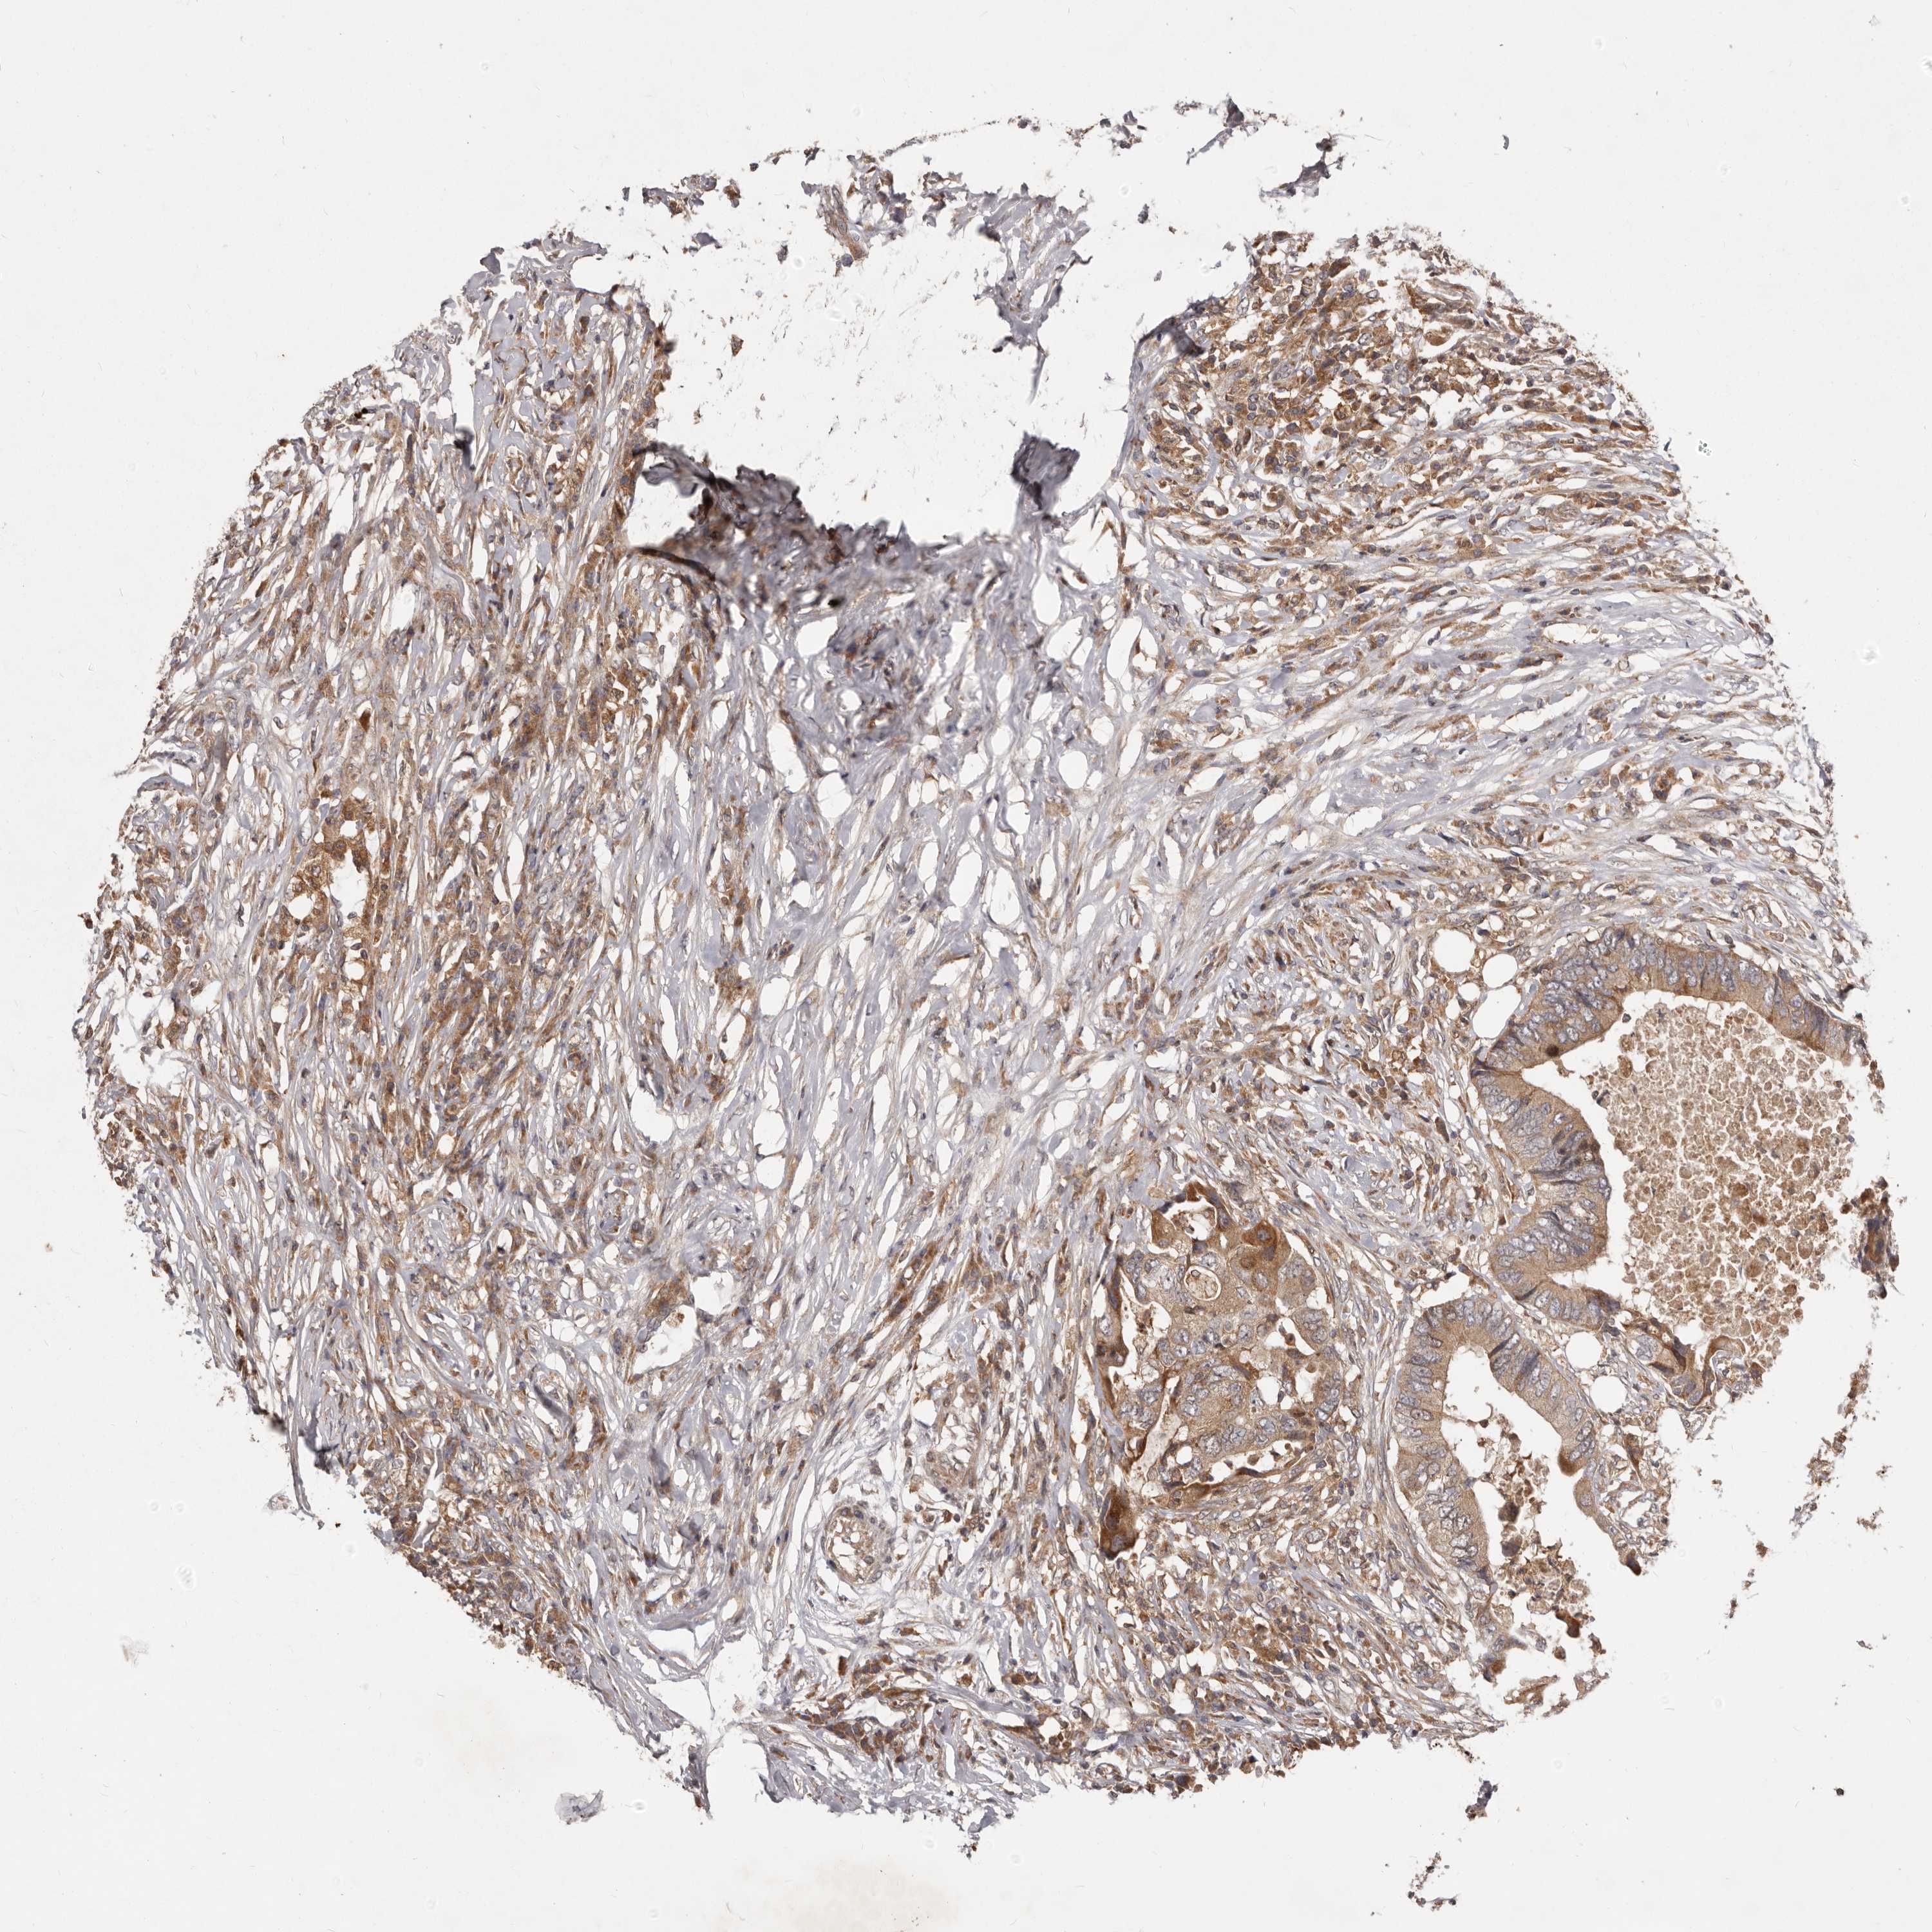

COLON ADENOCARCINOMA (VALIDATION) - Interactive survival scatter ploti

The Survival Scatter plot shows the clinical status (i.e. dead or alive) for all individuals in the patient cohort, based on the same data that underlies the corresponding Kaplan-Meier plots. Patients that are alive at last time for follow-up are shown in blue and patients who have died during the study are shown in red.

The x-axis shows the expression levels (FPKM) of the investigated gene in the tumor tissue at the time of diagnosis. The y-axis shows the follow-up time after diagnosis (years). Both axes are complimented with kernel density curves demonstrating the data density over the axes. The top density plot shows the expression levels (FPKM) distribution among dead (red) and alive patients (blue). The right density plot shows the data density of the survived years of dead patients with high and low expression levels respectively, stratified using the cutoff indicated by the vertical dashed line through the Survival Scatter plot. This cutoff is automatically defined based on the FPKM cutoff that minimizes the p-score. The cutoff can be changed by dragging the vertical line or by entering a cutoff value in the square labeled "Current cut-off".

Under the Survival Scatter plot the p-score landscape (black curve; left axis) is shown together with dead median separation (red curve; right axis). Dead median separation is the difference in median mRNA expression between patients who have died with high and low expression, respectively. It is calculated as follows: median FPKM expression of dead patients with high expression - median FPKM expression of dead patients with low expression. This is intended to aid the user in visually exploring custom cutoffs and the associated p-scores and dead median separation.

Individual patient data is displayed and can be filtered by clicking on one or more of the category buttons on the top of the page. Categories describing expression level and patient information include: high, low, alive, dead, female, male and tumor stages. The scale of the x-axis can be toggled between linear and log-scale by clicking on the "x log" button. Mouse-over function shows TCGA ID, patient information and mRNA expression (FPKM) for each patient.

& Survival analysisi

Kaplan-Meier plots summarize results from analysis of correlation between mRNA expression level and patient survival. Patients were divided based on level of expression into one of the two groups "low" (under cut off) or "high" (over cut off). X-axis shows time for survival (years) and y-axis shows the probability of survival, where 1.0 corresponds to 100 percent.

RNF187 is not prognostic in Colon Adenocarcinoma (validation)

Best expression cut offi

Based on the FPKM value of each gene, patients were classified into two groups and association between prognosis (survival) and gene expression (FPKM) was examined. The best expression cut-off refers the FPKM value that yields maximal difference with regard to survival between the two groups at the lowest log-rank P-value. Best expression cut-off was selected based on survival analysis .

When clicking on this number, the vertical dashed line indicating cut-off, the interactive survival plot, and the Kaplan-Meier curve will be adjusted to show results based on the best expression cut-off.

: 20.93

Median expressioni

Median expression refers to the median FPKM value calculated based on the gene expression (FPKM) data from all patients in this dataset. When clicking on this number, the vertical dashed line indicating cut-off, the interactive survival plot, and the Kaplan-Meier curve will be adjusted to show results based on the median expression.

: N/A

P scorei

Log-rank P value for Kaplan-Meier plot showing results from analysis of correlation between mRNA expression level and patient survival.

N/A

5-year survival highi

5-year survival for patients with higher expression than the expression cutoff.

For melanoma and glioma, 3-year survival is shown.

5-year survival lowi

5-year survival for patients with lower expression than the expression cutoff.

TCGA RNA samplesi

RNA-seq data is reported as average FPKM (number Fragments Per Kilobase of exon per Million reads), generated by the The Cancer Genome Atlas (TCGA) .

Normal distribution across the dataset is visualized with box plots, shown as median and 25th and 75th percentiles. Points are displayed as outliers if they are above or below 1.5 times the interquartile range. FPKM values of the individual samples are presented next to the box plot.

Average pTPM 17.2

Number of samples 486